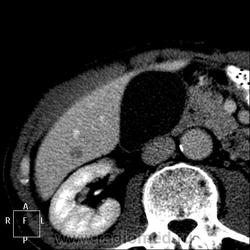

КТ: на нативной (без контраста) фазе захватила печень, выявлены изменения печени и левой почки.

Левая почка:

Видимая часть изменения печени в арт.фазу:

---почка:

Печень: